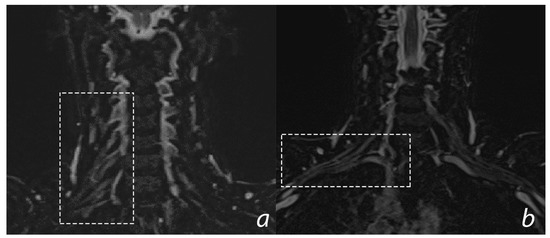

6.3. Imaging

- Gasparotti, R. New techniques in spinal imaging. Neuroradiology. 2011, 53 (Suppl. 1), S195–S197. [Google Scholar] [CrossRef]